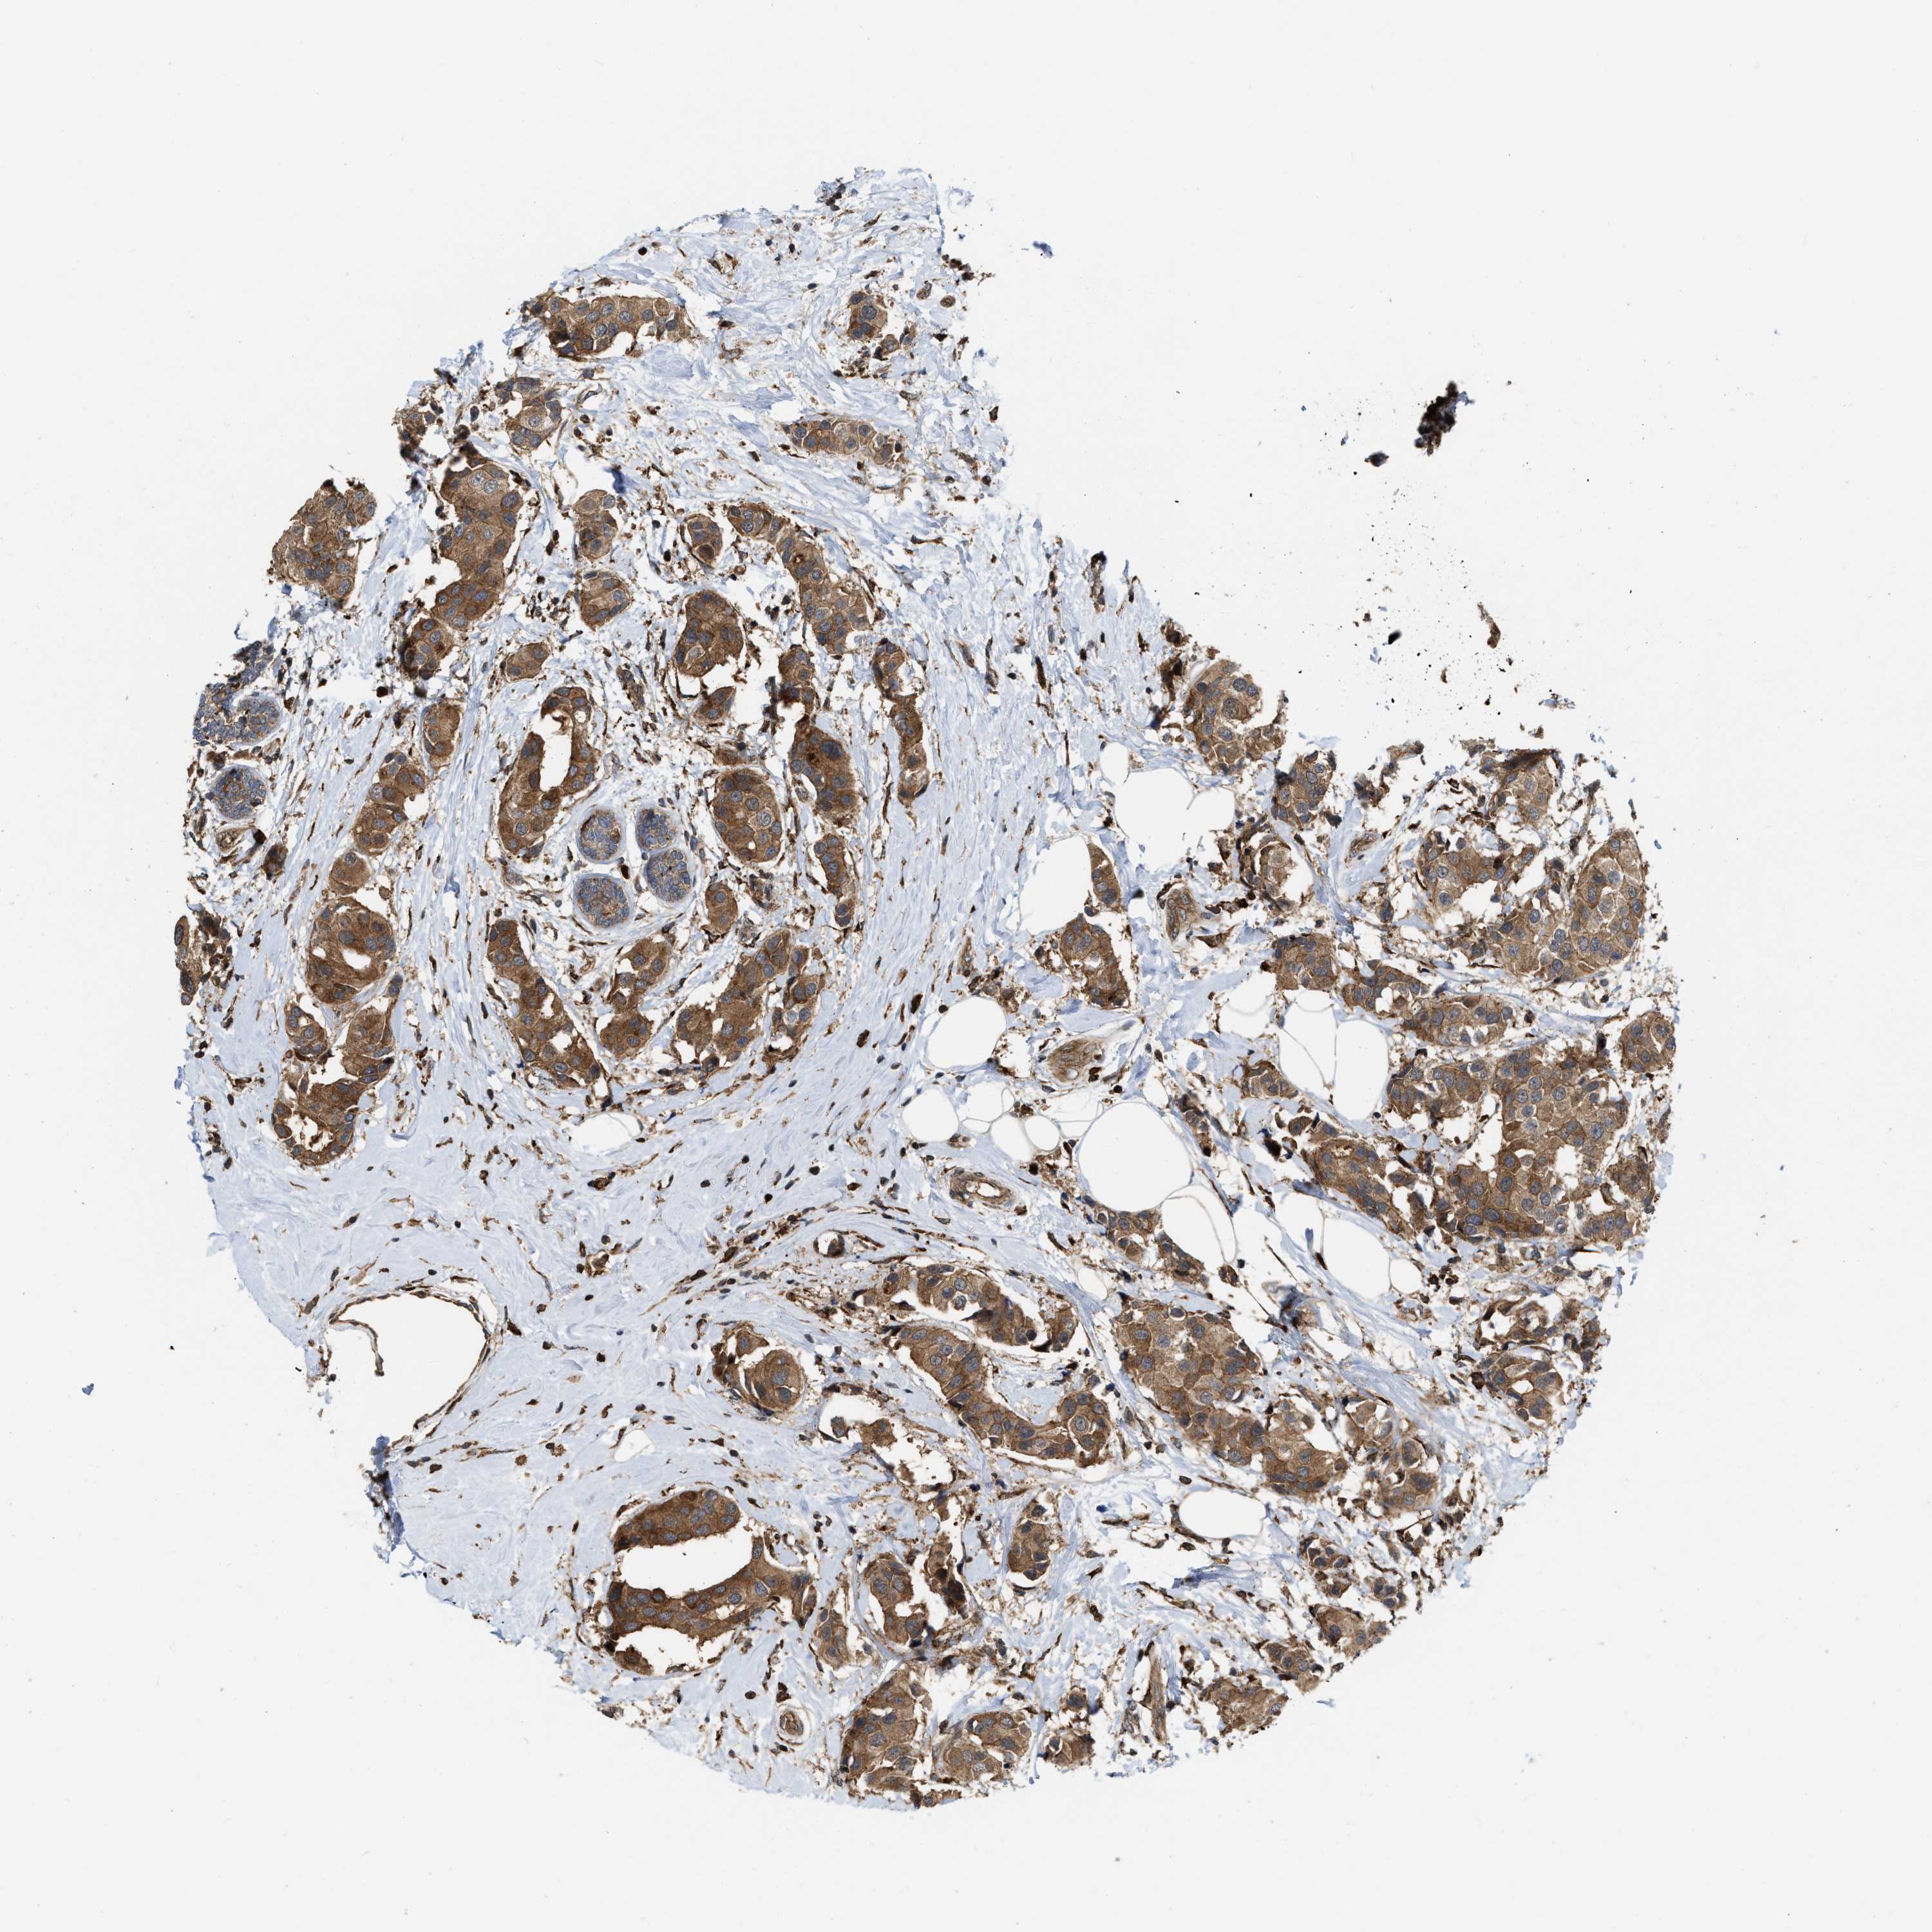

CANCER BREAST CANCER Show tissue menu

BRCA TCGA BRCA VALIDATION PROTEIN EXPRESSION